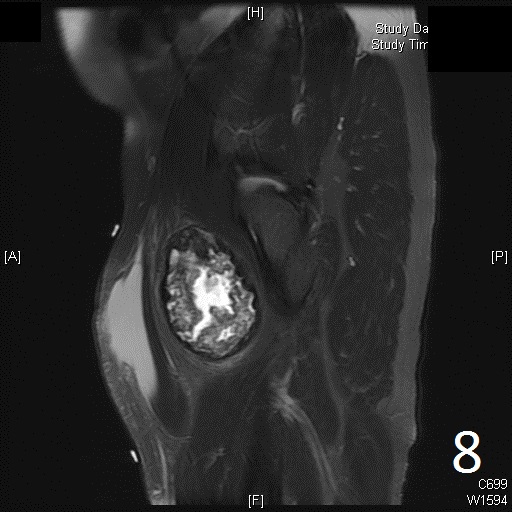

• 60% of fibrosarcomas are intramuscular (Fig. 2, 3, 5, 6, 7, 8)

• Well defined heterogenous mass on T2W (Fig. 4, 9)

• Necrosis and hemorrhage are common, especially in high grade tumors

• On gadolinium, viable areas of tumor enhance, while areas of significant necrosis and hemorrhage do not enhance (Fig. 6).

Fig. 5-9: Axial and sagittal (Fig. 6) MRI shows a fibrosarcoma in the proximal quadriceps muscle that is isointense to muscle on T1W images, and a heterogeneous on T2W FS (Fig. 7, 8). The patient was treated with preoperative chemotherapy and the mass underwent extensive necrosis. The mass does not show any enhancement with contrast due to the extensive necrosis. There is only peripheral enhancement with contrast on T1W FS (Fig. 9).